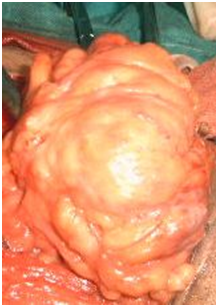

An 82year old male presented with painless swelling of right groin of 18months duration for which he was asymptomatic. General physical as well as systemic examination was normal. Local examination showed a 17×11×7.3 centimeter swelling, with thinned overlying skin, soft, non tender, with restricted mobility, having negative cough impulse and the transillumination test (Figure 1). Ultrasonography showed a hyper echoic lesin. Fine needle aspiration yielded adiposities. Patient had excision with intraoperative swelling, soft, yellowish with adhesions with adjacent structures which were easily released, weighing about 756grams (Figure 2) (Figure 3). Post operative period period was uneventful and no recurrence seen in follows up of 11months.

Figure 2 Showing Lipoma on Cord.

Figure 3 Showing excised specimen.